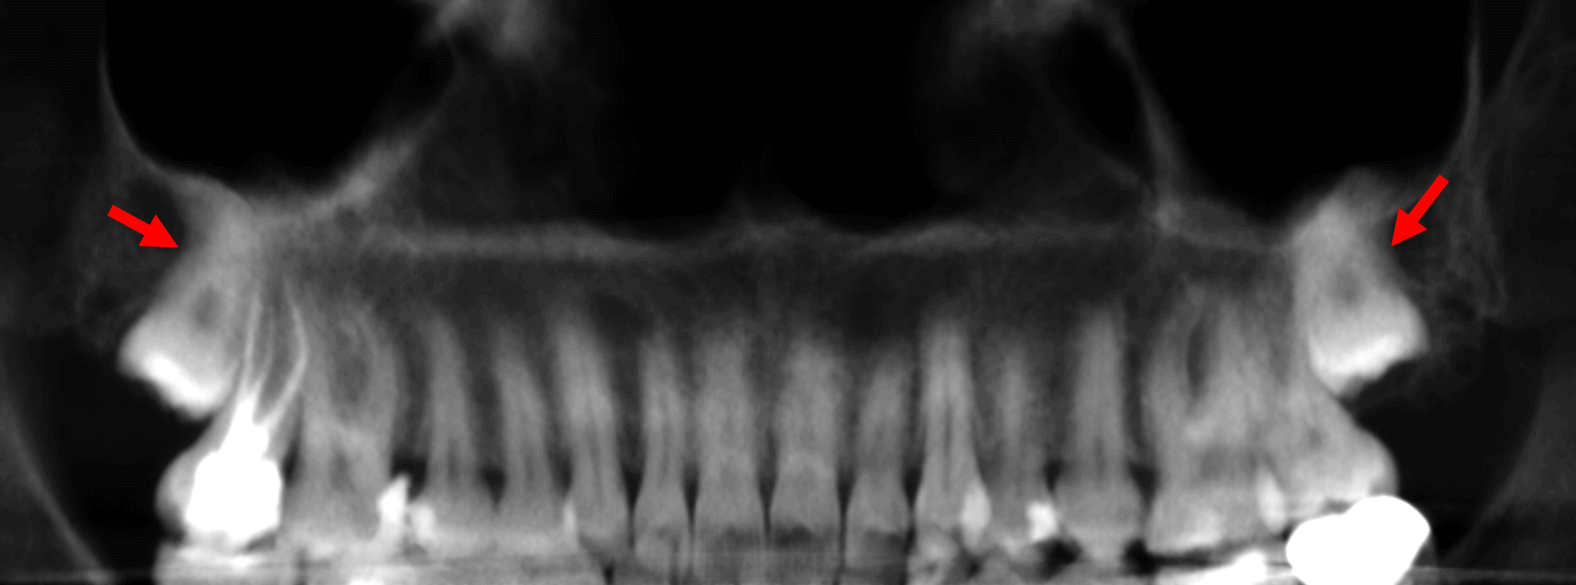

En cortes axiales (Fig.2) se observan las raíces de los terceros molares (flechas rojas, superior) en estrecha relación con el seno maxilar. En el corte inferior se observan las coronas de los órganos dentarios 18 y 28.